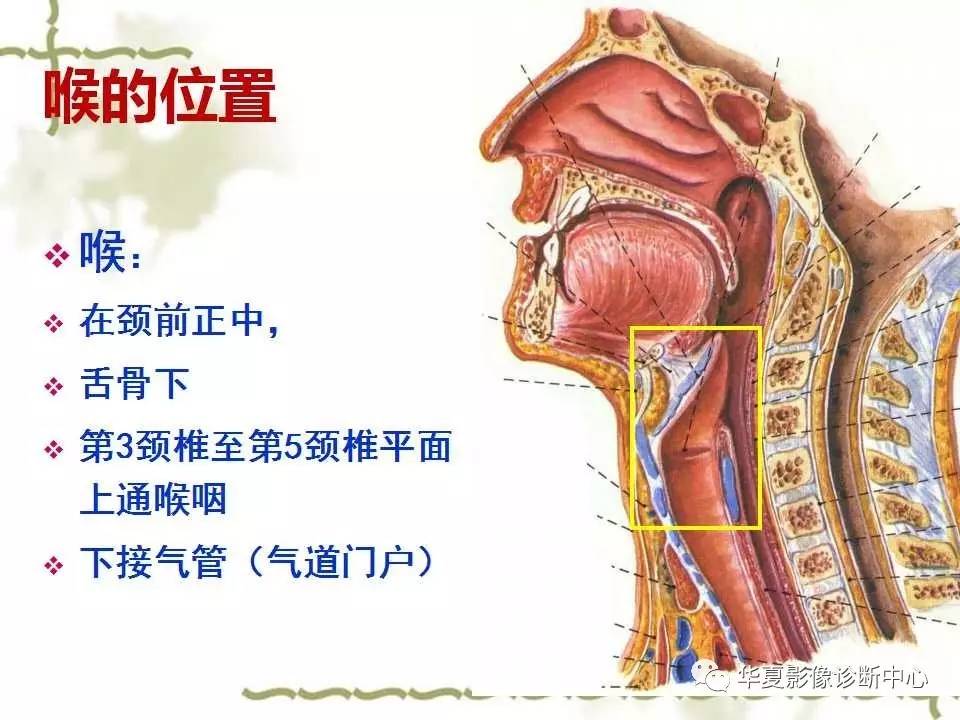

Ppt 喉癌powerpoint Presentation Free Download Id 3651007